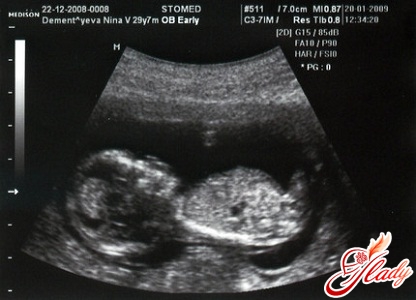

Беременность 14 неделя: узи. На этой неделе у девочек яички опускаются в тазобедренную часть, а у мальчиков появляется простата. Хотя гениталии уже можно охарактеризовать как женские и мужские, при УЗИ их еще невозможно различить. Ребенок уже производит мочу и кувыркается. Однако на этом сроке беременности будущие мамочки еще не могут чувствовать движений своего малыша.

Если у вас беременность 14 неделя, то на этом сроке ваш малыш заметно подрос и стал размером с грушу. Его длина примерно 80-113 мм, а вес — около 25 грамм.